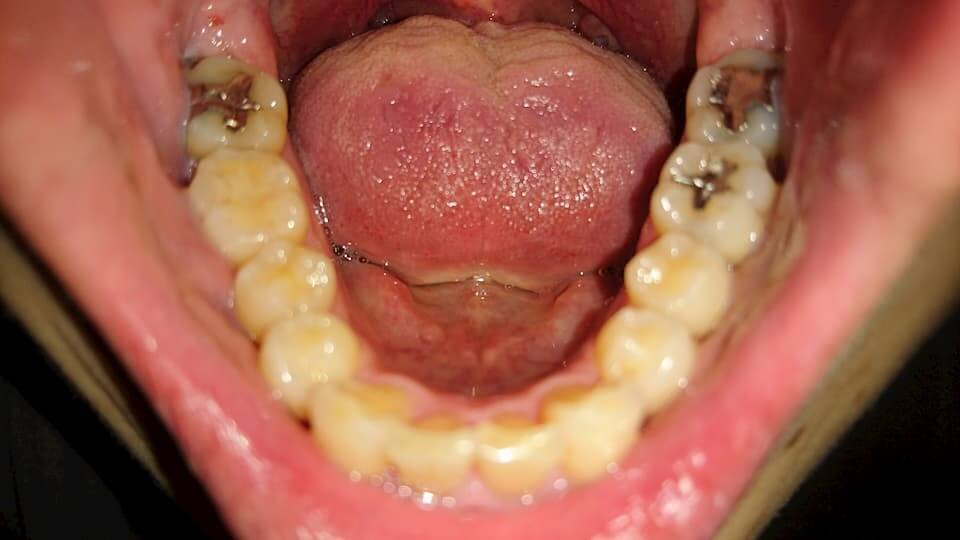

歯の写真